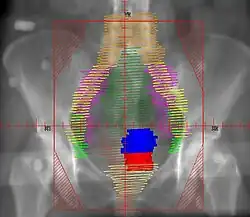

Example of an AP radiation therapy treatment field for Stage IB2+ Cervix used at Tufts/Brown residency program. Actual patient contours should guide field design.

• Superior border: L4/L5. If common illiac LN involvement, superior border should extend to L3/L4 or higher to cover the disease with 3 cm margin

• Inferior border: inferior edge of pubic ramus. If vaginal involvement, inferior border should extend 3-4 cm past the vaginal extent of the disease, as marked by a gold seed

• Lateral borders: ~2cm lateral to bony pelvis, in order to cover lymph nodes

• Red: cervix; Blue: uterus; Khaki: bladder; Brown: rectum

• Orange: common illiac LNs; Yellow: external illiac LNs; Light Green: obturator LNs; Purple: internal illiac LNs; Dark Green: presacral LNs